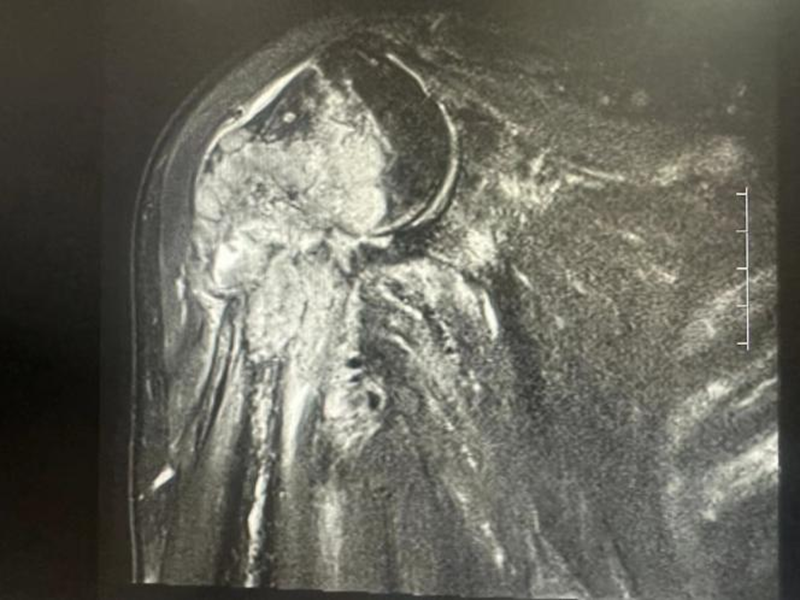

患者张某,68岁,因右肩关节疼痛伴活动受限半年入院,诊断结果为“右肱骨转移性骨肿瘤并病理性骨折”。吴军主任团队为其施行了“肱骨上段肿瘤切除,肱骨上段及半肩置换、完整肩袖修复术”。术后患者疼痛消失,右上肢恢复了90%的功能,能够满足日常活动所需,患者及家属十分满意。

术前:右肱骨头、肱骨上端转移癌,合并骨折

术后:术中切除肿瘤段骨,切除病变软组织,重建肩袖结构